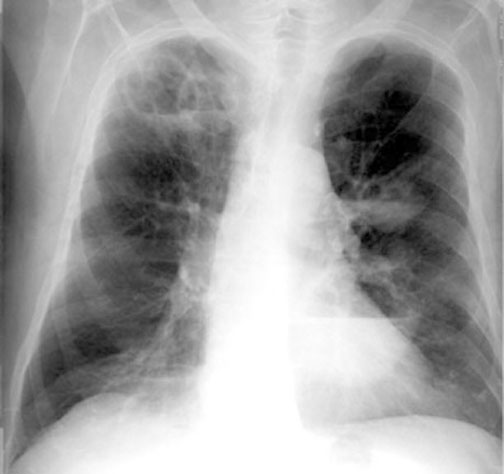

Case 15 Labeled Image What are the characteristics of tuberculous cavity?